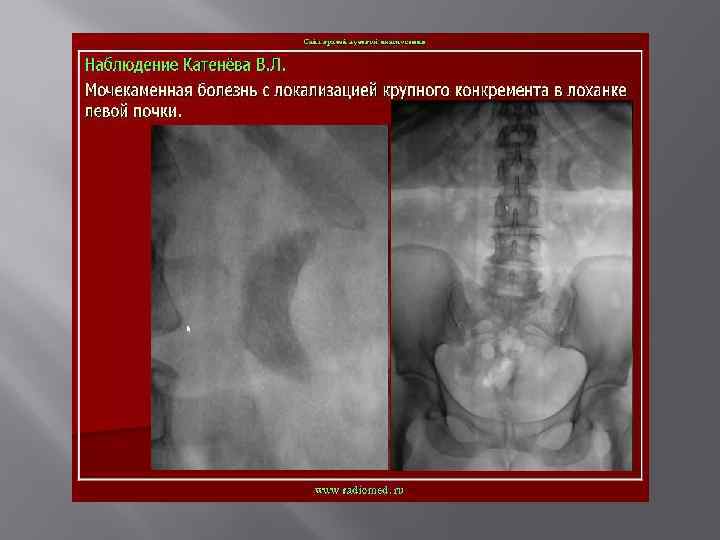

Мочекаменная болезнь

Мочекаменная болезнь ХРОНИЧЕСКИ ПРОТЕКАЮЩЕЕ ЗАБОЛЕВАНИЕ ХАРАКТЕРИЗУЮЩЕЕСЯ НАЛИЧИЕМ В ПОЛОСТНОЙ СИСТЕМЕ ИЛИ ПАРЕНХИМЕ КАМНЕЙ, ФОРМИРУЮЩИХСЯ ИЗ СОСТАВНЫХ ЧАСТЕЙ МОЧИ. Составляют 30 -40% всех хирургических заболеваний. Различают одиночный камень, множественные лоханочные и комбинации лоханочного камня с чашечковым или поренхиматозными. Выделяют понятие рентгенонегативного камня, т. е. камень который не даёт тени на рентгенограмме.

Экскреторная урография -рентгненегативные камни- дефект наполнения - Рентгенпозитивные камни-тень камня усиливается

Коралловидные камни